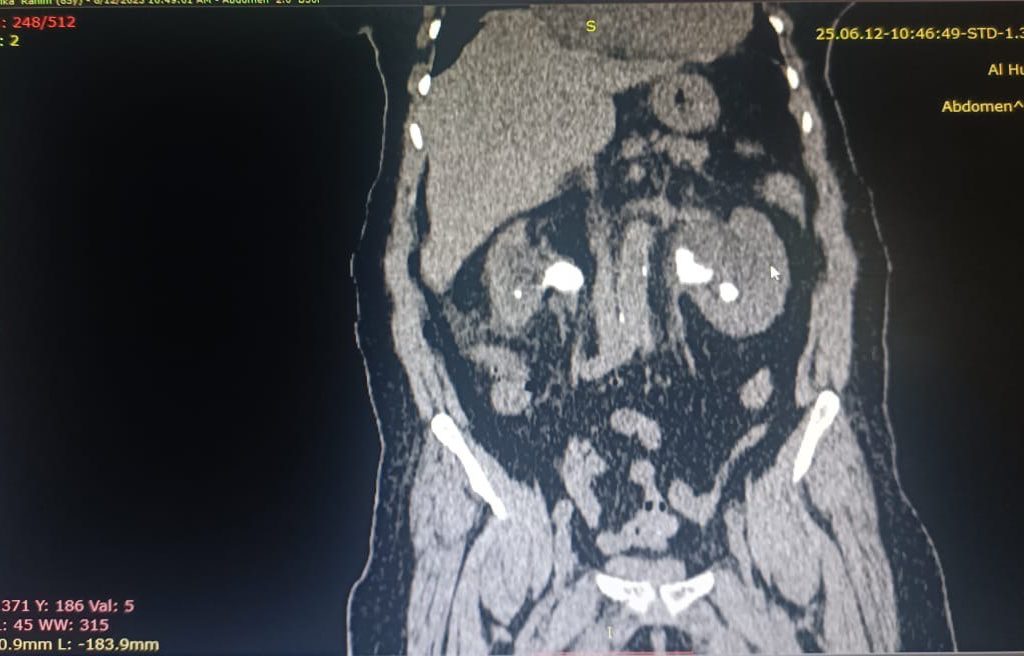

“بعد استقرار حالتها، وضعنا خطة علاجية متكاملة تضمنت إجراء عمليات ناظورية متتابعة. قمنا أولًا برفع حصى الكلية اليسرى بتقنية استخراج الحصوات عبر الجلد (PNL) من خلال فتحة صغيرة لا تتجاوز 1 سم، وهي تقنية دقيقة تسرّع التعافي وتقلل المضاعفات.”

“بعد شهرين أجرينا عملية رفع حصى الكلية اليمنى باستخدام تقنية ناظور الحالب والكلية المرن الحديثة، والتي مكنتنا من إزالة الحصوات بكفاءة عالية دون جراحة تقليدية.”